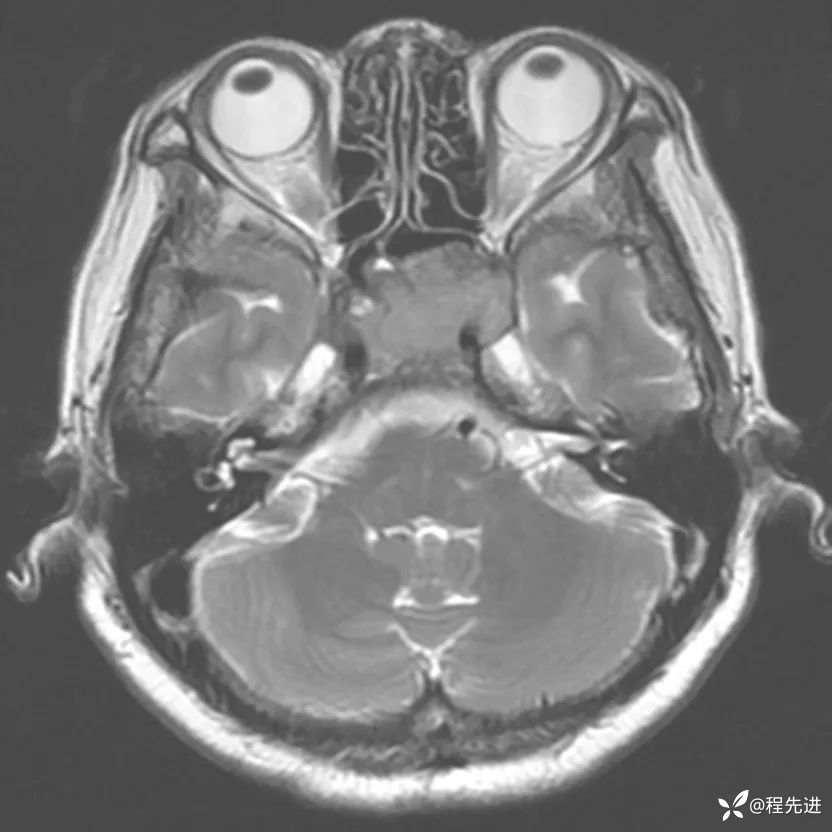

简要病史:外伤检查发现颅底占位

MRI平扫+增强: